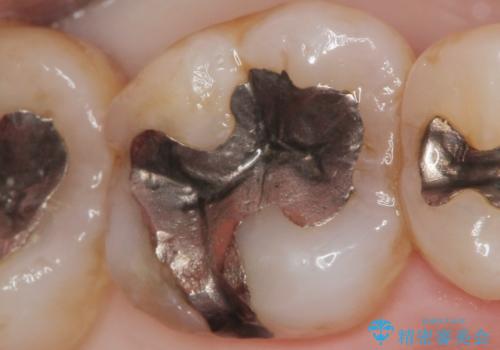

- 銀歯で詰めたところが引っ掛かるようになり舌で触ると気になる、再治療を希望され来院されました。

銀歯の劣化が見られたので化学的に安定し、長期的な予後の見込めるゴールドインレーを用いて再修復することとしました。